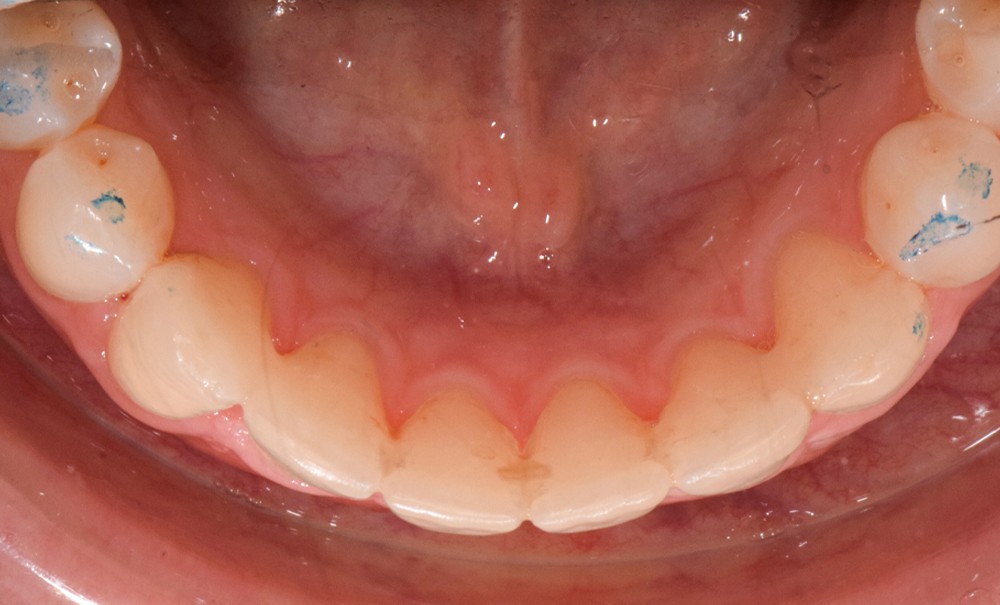

Par exemple, le retraitement d’un patient atteint d’un « Syndrome du fil » [2, 3], au vu de l’état des connaissances imparfaites de l’étiologie de cette situation, méritera une réflexion pour trouver un système de confiance. Une fibre collée est l’une des solutions sécurisantes (fig. 1). Mais, si la langue n’est pas stabilisée au repos comme en fonction, un dispositif amovible type Spring Retainer sera préférable.